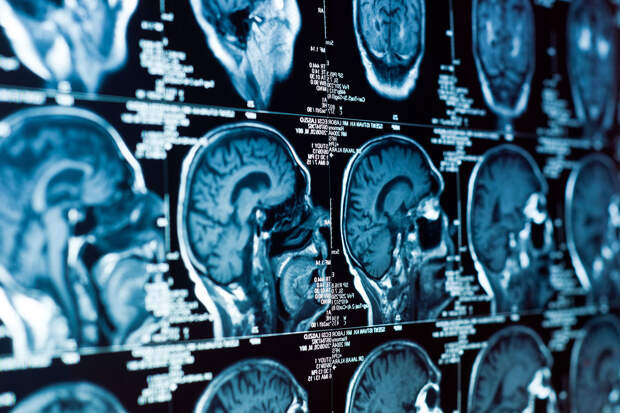

Ученые из Гарвардской медицинской школы разработали инструмент на базе искусственного интеллекта, который способен с высокой точностью различать два типа опухолей головного мозга: глиобластому и первичную лимфому центральной нервной системы (ПЛЦНС). Результаты исследования опубликованы в журнале Nature Communications (NatCom).

Новая система получила название PICTURE (Pathology Image Characterization Tool with Uncertainty-aware Rapid Evaluations). Тесты показали, что модель работает с почти идеальной точностью — свыше 98% — даже в сложных условиях интраоперационной диагностики. Этот метод медицинского обследования применяется непосредственно во время хирургического вмешательства.

Во время операций нейрохирурги часто используют так называемые замороженные срезы опухоли для быстрой оценки. Однако из-за изменений клеточной структуры при заморозке и визуального сходства между типами рака возможны диагностические ошибки.